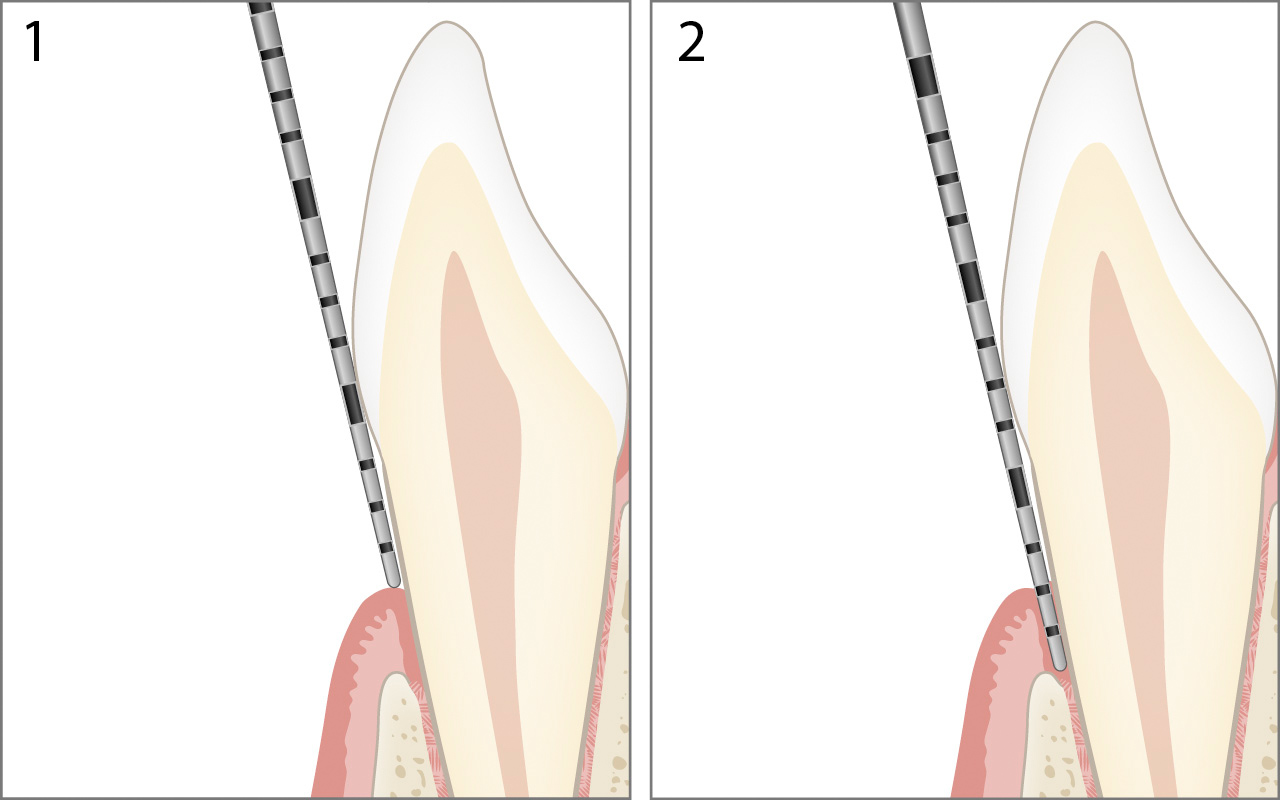

Gingivarezession

Bei der Gingivarezession liegt der Gingivalrand apikal der Schmelz-Zement-Grenze. Der gemessene Wert für "Margo Gingivae" 1 wird dann mit einem negativen Vorzeichen angegeben.

Die Berechnung des Attachmentniveaus in der oben gezeigten Abbildung lautet:

Attachmentniveau 6mm = Sondierungstiefe 2mm – Margo Gingivae -4mm